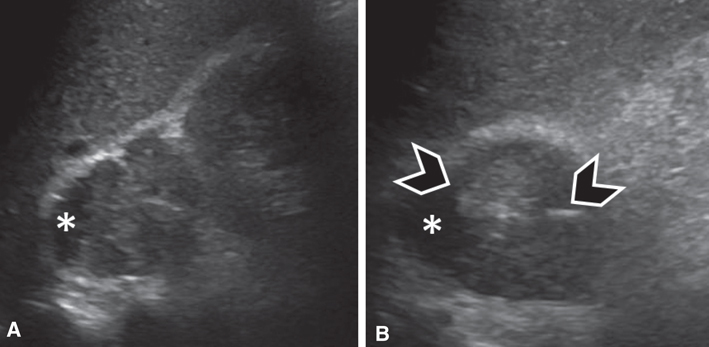

Ultrasound

The adrenal glands are easily detected on ultrasound in neonates, but become more challenging to visualize in older children and adults. Adrenal and retroperitoneal lesions may or may not be seen on ultrasound, depending on the lesion size, patient body habitus, and the operator. Ultrasound is not the modality of choice for evaluating or screening for adrenal lesions, pheochromocytomas, or paragangliomas in adults. When detected on ultrasound, pheochromocytomas tend to be of heterogeneous echogenicity and can be partially cystic or necrotic (Figure 2).

Fig 2

Figure 2 Pheochromocytoma in a 45-year-old male patient. (A) Sagittal and (B) axial ultrasound images of the right adrenal region demonstrate a lesion of heterogeneous echogenicity between the liver (top portion of A and B) and the right kidney (right side of A). The lesion contains a cystic component (asterisk) as well as echogenic foci (arrowheads), suggesting calcifications.